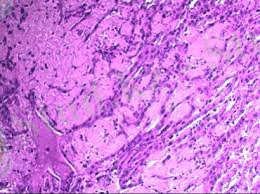

Гистопрепарат. Гельминт түйінінің айналасындағы дәнекер тінінің капсуласының гиалинозы

Микроскоптың шамалы ұлғаюымен кәдімгі радиалды орналасқан сәулелері бар сақталған бауыр тіндерінің арасында дөңгелек және дұрыс емес дөңгелек пішінді түзілімдер көрінеді-ортасында қызғылт-қызғылт құрылымсыз эозинофильді массадан тұратын түйіндер, оларда мыжылған пикнотикалық ядролар орналасқан. Орталықтағы кейбір түйіндерде гематоксилинмен көк-күлгін түске боялған әк сақталған. Түйіндегі эозинофильді массаның айналасында ұзартылған ядролар көрінетін қызғылт біртекті талшықты дәнекер тінінен тұратын кең белдеу бар. Дәнекер тінінің сымдары мен сақталған бауыр тіндерінің арасында эозинофильді лейкоциттердің кластерлері көрінеді.